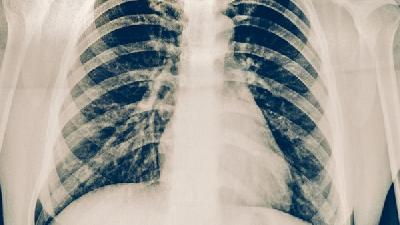

肺炎到底能不能治愈